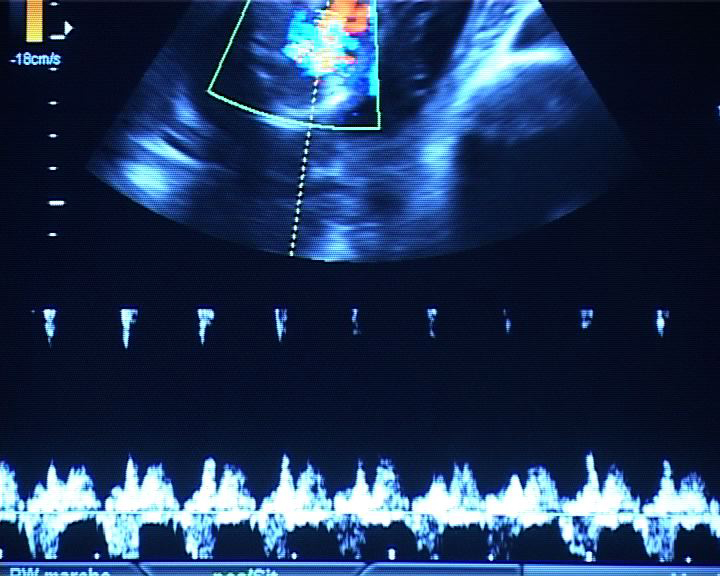

Que se passe-t-il derrière ces portes, ces couloirs d'hôpital aux couleurs saturées ? Qu'éprouve-t-on à cet endroit, avec ces jeunes femmes en tenue rose passé, dans le battement et le souffle des machines, la douleur ? Parmi les tuyaux, les poches, les lumières, les chiffres et les tracés des appareils et des alarmes ? Les cris, l’abstraction des vocables techniques, les tensions, les frottements, et la douceur aussi des gestes silencieux ? Quels interstices faut-il regarder pour assister à une cérémonie secrète faite de douleur, d'efforts, de concentration, de rythmes qui s'accélèrent, de voix qui encouragent, et où la délivrance ne va pas sans le regard d’adieu minutieux à ce qu'on doit laisser ?

Née en 1976 à Paris, Pauline Higgins suit le double chemin de l'ethno-anthropologie et de la maïeutique (sage-femme). Ces deux désirs sont nés au Sénégal avant d'être enrichis par l'EHESS et son étude de terrain "Une maternité de brousse en plein Paris" qui montre que l'ignorance des marquages rituels peut, avec réserve, faire place à l'altérité. Pauline travaille sur le toucher, le tact, le "care", l'attention, l'intime. "Passage", réalisé avec les Ateliers Varan, interroge la technologie entourant l’accouchement. "Vagues", conçu avec la Fémis, est un essai sur la mémoire généalogique. Dans les mangroves du Siné-Saloun, elle précise son intérêt pour les systèmes de guérissage, et l’intentionnalité des gestes. "Naître vient de nature", adressé à l’équipe de Bruno Latour qu'elle rejoint, questionne la "culture de la nature" chez les sages-femmes. "Toucher c'est voir", filmé avec pudeur, fait entendre leurs gestes et leurs intentions. "R6/2 ou comment faire connaissance avec les animaux d'expérimentation", performance collective, veut donner un nom à ces non-humains, invisibles médiateurs sacrifiés. Pauline expérimente les périodes liminales, floues, entre nature et culture. Son projet de film actuel interroge l’"être près", l’ombre, l’obscurcissement, l’obfuscation.